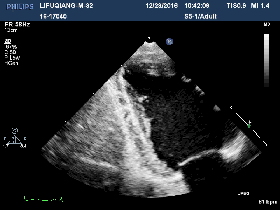

2016-12-20

◆BNP:115pg/ml

◆肌酐: 317umol/L

◆心超:

▶左房左室内径较前相仿

▶左室收缩功能整体减退,LVEF 43%

▶左室舒张功能未见异常E/E`=8

▶左室下壁心尖段见1处条索样回声,随血流甩动,大小约8mm

▶右房右室内径正常,TAPSE 17mm

▶心包腔内未见无回声区